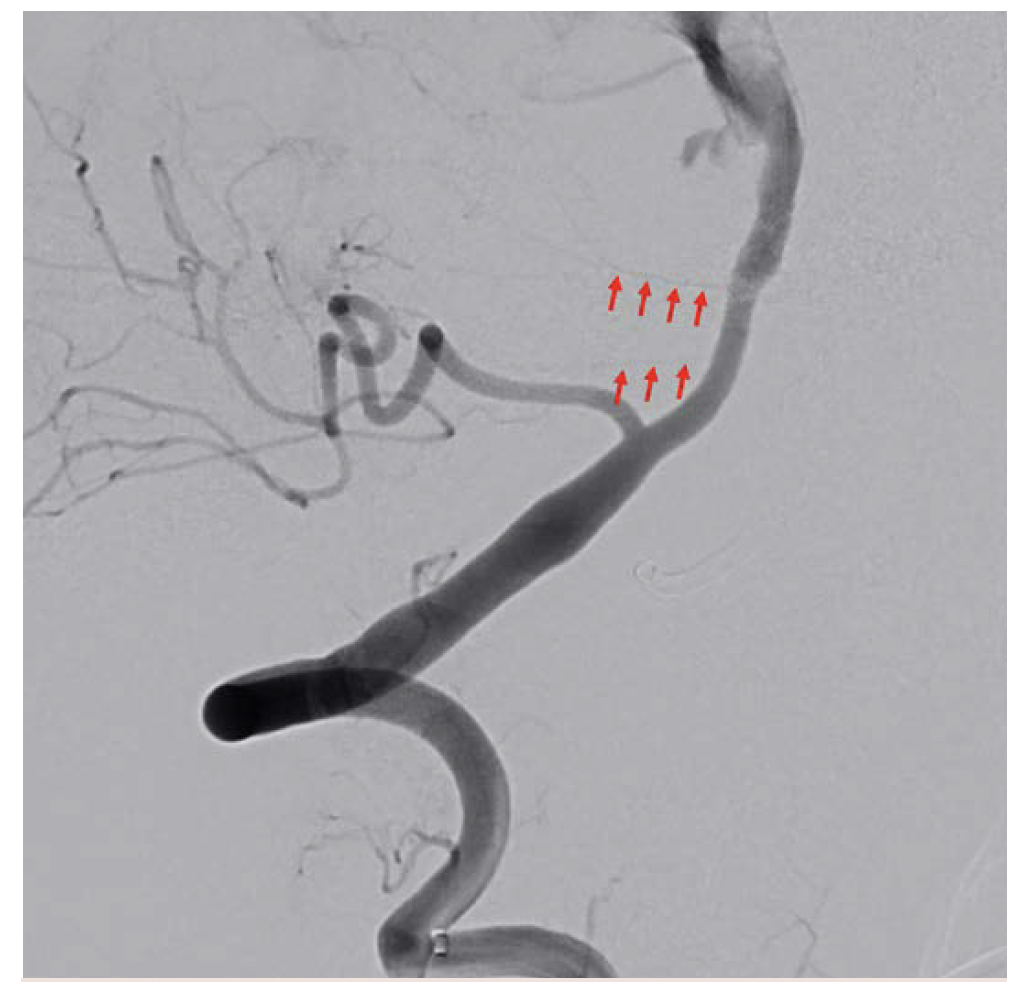

The original plan was to coil off the right vertebral artery distal to PICA. However, the imaging resolution of the ARTIS icono enabled visualization of critical medullary perforators distal to the PICA origin (Figure 16). The plan was therefore modified to coil off the vertebral distal to the most distal of these perforators. The distal right vertebral artery was successfully embolized distal to the perforators (Figure 17).